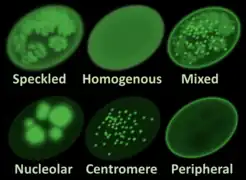

CREST syndrome is associated with detectable antibodies against centromeres (a component of the cell nucleus), and usually spares the kidneys (a feature more common in the related condition systemic scleroderma). If the lungs are involved, it is usually in the form of pulmonary arterial hypertension.

CREST syndrome involves the production of autoimmune anti-nuclear and anti-centromere antibodies, though their cause is not currently understood. There is no known infectious cause.

CREST is not easily diagnosed as it closely mimics symptoms of other connective tissue and autoimmune diseases. Diagnoses are usually given when a patient presents two or more of the five major clinical symptoms.[5] Additionally, blood exams can be given to test for a positive ANAs and ACAs or skin biopsies can be given to help confirm a diagnosis.[6]